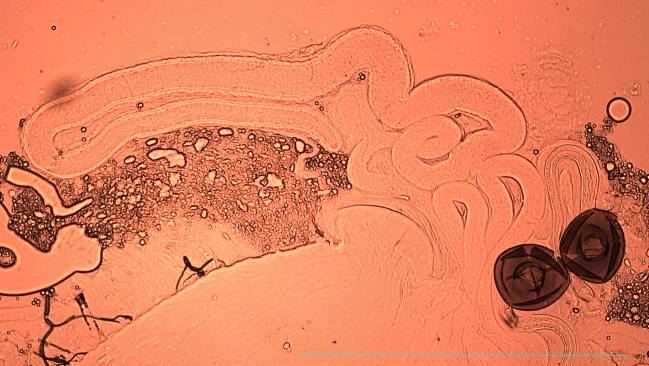

Se basa en extraer células del sistema inmunitario de los pacientes, en este caso las células T, que se modifican genéticamente para que expresen un receptor de antígeno quimérico (CAR) y posteriormente se vuelven a infundir al paciente. En el caso de los tumores, este cambio permite que las células modificadas ataquen a las células tumorales.

“En el lupus, las células CAR-T eliminan los linfocitos B de los pacientes que son los responsables de producir los anticuerpos que causan el lupus”, explica Pere Barba, director del Programa CAR-T del Servicio de Hematología del Hospital Universitario Vall d’Hebron e investigador del grupo de Hematología Experimental del VHIO.